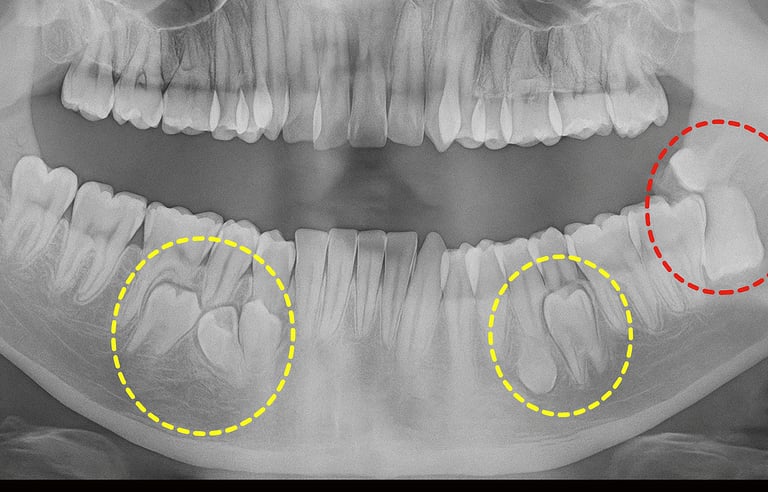

Q2. How do I know if I need wisdom tooth removal?

π If you have pain, swelling, gum infection, or misalignment, wisdom tooth extraction may be necessary.